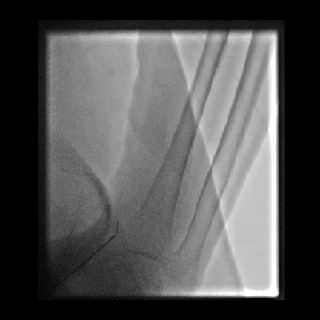

1. 患者仰卧位,左手内旋自然状态置于腹部,左手弯向病人的右腹股沟,左上肢常规消毒铺巾,暴露左手。左侧鼻烟壶处注射2ml利多卡因,使用微穿针以改良的Seldinger法向左侧远桡动脉动脉搏动最强处穿刺,穿刺成功后先置4F短鞘,将猪尾导管选至降主动脉后引入加硬导丝,再交换引入Cordis 6F薄壁长鞘。

动脉长鞘怎么置入桡胜一筹丨杨敏教授团队:应用Brite Tip Radianz长鞘经远桡动脉治疗肾动脉狭窄一例_https://www.jmylbn.com_新闻资讯_第18张

动脉长鞘怎么置入桡胜一筹丨杨敏教授团队:应用Brite Tip Radianz长鞘经远桡动脉治疗肾动脉狭窄一例_https://www.jmylbn.com_新闻资讯_第19张